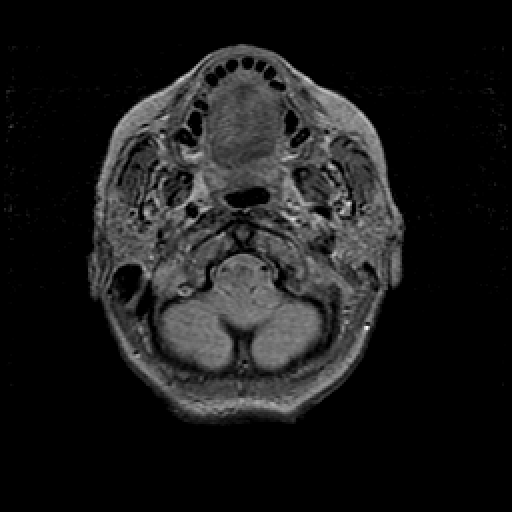

Proton density-weighted structural MR: Slice 5

Slice 5